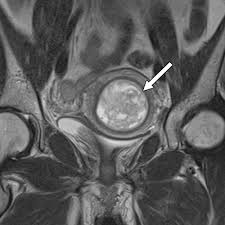

Mri Is Indicated In Patients With Malignant Forms Of Gestational Trophoblastic Neoplasia Gtn For An Assessment Of Tumor Vasc Rings For Men Mri Representation